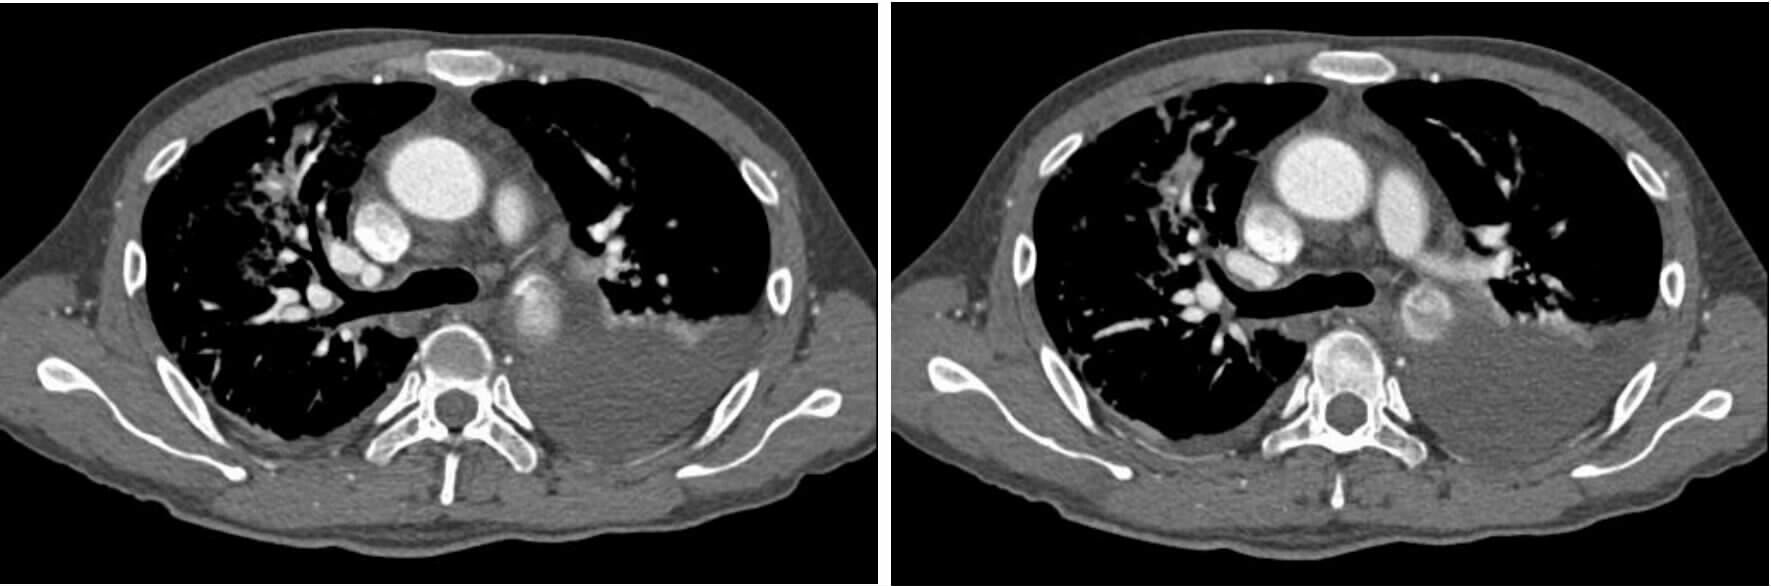

2 结果37例钝性胸主动脉损伤,CTA征象表现为内膜瓣、轮廓异常、血栓、动脉收缩、假性动脉瘤、主动脉夹层6种情况。①内膜瓣:内膜瓣为增强的主动脉管腔内可见一个或多个弧形弱化区(图 1)。②主动脉轮廓异常:表现为主动脉管壁或轮廓不规则,圆形的主动脉横切面发生变化,(图 2)。③假性动脉瘤:指主动脉壁破裂出血,形成主动脉壁外的血肿,主动脉管腔与不规则瘤腔结合处呈锐性边缘(单侧或双侧),(图 3)。④主动脉夹层:内膜片和主动脉真假两腔形成是诊断夹层动脉瘤的基本征象。内膜片将血管分为真假两个腔隙。增强早期真腔密度高于假腔,随时间延迟,假腔密度逐渐增高,假腔密度可等于或高于真腔,(图 4)。⑤动脉收缩表现为损伤节段主动动脉直径小于正常节段动脉直径(图 5)。⑥血栓;主动脉腔内息肉样低密度区(图 6)。本组37例钝性胸钝性胸主动脉损伤患者,CTA征象存在内膜瓣34例(91.8%),主动脉轮廓改变或腔异常37例(100%),动脉收缩17例(45.9%),主动脉夹层10例(27.0%),假性动脉瘤21例(56.7%),血栓1例(2.7%)。

| 图 1 主动脉峡部损伤内膜瓣征象 Figure 1 Intimal flap sign of aortic isthmus injury |

| 图 2 主动脉峡部损伤动脉轮廓发生改变 Figure 2 Artery contour changes of aortic isthmus injury |

3.3 CTA诊断钝性胸主动脉损伤的直接征象在选择的这组病例中,手术或主动脉造影均证实存在钝性胸主动脉损伤。CTA显示钝性胸主动脉损伤的征象包括内膜瓣、轮廓改变、假性动脉瘤、主动脉夹层、主动脉收缩及血栓形成。上述CTA征象可提示钝性主动脉存在损伤,是诊断钝性胸主动脉损伤的重要依据,对钝性胸主动脉损伤具有定性诊断价值。在阅CTA片时,注意观察有无上述征象存在,及时诊断钝性胸主动脉损伤。